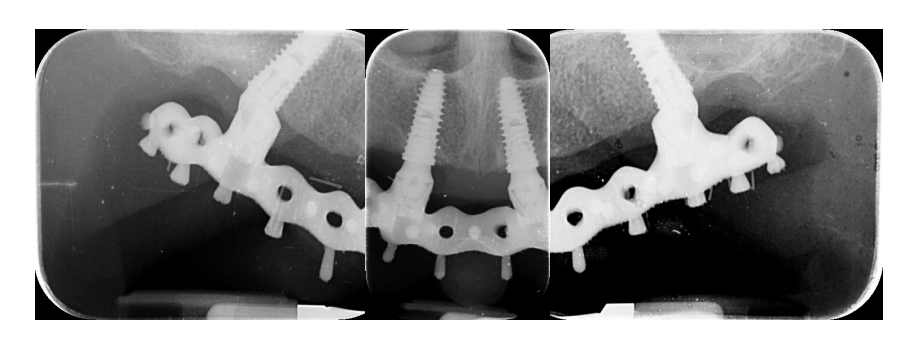

- Точность проверялась с помощью прямого зрения и тактильного ощущения, выполняемого путем чередующегося давления на алюминиевую пробу, а затем на окончательную металлическую каркасную конструкцию (Техника чередующего давления), закрепленную без винтов, чтобы определить, происходит ли какое-либо движение. Кроме того, тест с одним винтом, предложенный Джемтом и его коллегами, проводился в случае возникновения сомнений. Никаких несоответствий радиопрозрачной алюминиевой пробы, закрепленной только одним затянутым винтом, не наблюдалось. При необходимости были сделаны периапикальные рентгенограммы. Тот же оператор (MT) проводил оба теста с использованием микроскопического увеличения (10× до 16×);

После этого эстетическая примерка была снята. Четыре новые скан-аналоги были подключены к временным абатментам и отсканированы вне рта пациента с помощью обычного экстраорального сканера (Рисунок 21). Прежде чем была изготовлена окончательная CAD/CAM конструкция, клинически и радиографически была протестирована радиопрозрачная алюминиевая конструкция. После этого было выполнено перекрестное монтаж окончательной реставрации (позиция имплантата) с функционализированной временной реставрацией, а также с оригинальным планом. На следующем приеме титановая CAD/CAM конструкция была протестирована в рту пациента. В конце концов, была доставлена фиксированная, удерживаемая винтом, имплантоподдерживаемая реставрация, изготовленная из титана, с композитом в качестве облицовочного материала (Рисунки 22–24). Композит был выбран из-за своей прочности и способности к поглощению ударов. Лингвализированный окклюзия была спроектирована для всех окончательных реставраций, с использованием анатомических зубов для верхнего протеза и модифицированных неанатомических или полуанатомических зубов для нижних протезов.

Все имплантаты успешно остеоинтегрировались, и все окончательные протезы функционировали к концу данного предварительного отчета, что привело к 100% выживаемости имплантатов и протезов. Не было зафиксировано биологических и технических осложнений. Однако одна из пяти оттисков была выполнена повторно из-за неточности алюминиевой ложки. В этом случае алюминиевая ложка была разделена, и две части были зафиксированы с использованием специальной светокурящей смолы для имплантатов (EZ-Pattern LC), полимеризованной под УФ/ВИЗ светом 350–480 нм. Кроме того, был сделан гипсовый оттиск. После доставки окончательных реставраций механических осложнений не наблюдалось. Все пациенты были полностью удовлетворены как функциональными, так и эстетическими результатами и были готовы повторить процедуру снова.